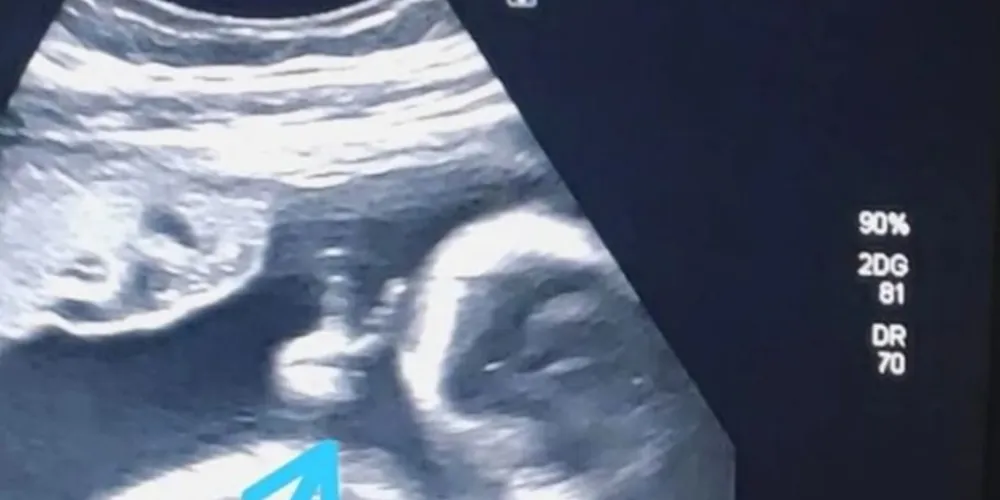

Bebê faz ‘V de vitória’ durante ultrassom e pai vê sinal divino

Ao acompanhar o exame de ultrassonografia de sexto mês do primeiro filho, Felipe Moreira dos Santos, de 32 anos, teve um grata surpresa: o bebê fez um ‘V de vitória’ com a mãozinha, dentro do útero. O rapaz, que é morador de Guarujá, no litoral de São Paulo, encarou como um sinal divino, já que enfrenta um câncer raro no baço, informa o Portal G1 de Santos.